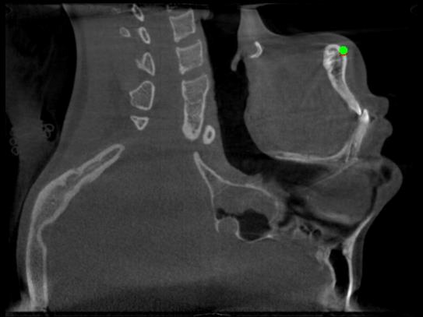

Detecting 3D landmarks on cone-beam computed tomography (CBCT) is crucial to assessing and quantifying the anatomical abnormalities in 3D cephalometric analysis. However, the current methods are time-consuming and suffer from large biases in landmark localization, leading to unreliable diagnosis results. In this work, we propose a novel Structure-Aware Long Short-Term Memory framework (SA-LSTM) for efficient and accurate 3D landmark detection. To reduce the computational burden, SA-LSTM is designed in two stages. It first locates the coarse landmarks via heatmap regression on a down-sampled CBCT volume and then progressively refines landmarks by attentive offset regression using multi-resolution cropped patches. To boost accuracy, SA-LSTM captures global-local dependence among the cropping patches via self-attention. Specifically, a novel graph attention module implicitly encodes the landmark's global structure to rationalize the predicted position. Moreover, a novel attention-gated module recursively filters irrelevant local features and maintains high-confident local predictions for aggregating the final result. Experiments conducted on an in-house dataset and a public dataset show that our method outperforms state-of-the-art methods, achieving 1.64 mm and 2.37 mm average errors, respectively. Furthermore, our method is very efficient, taking only 0.5 seconds for inferring the whole CBCT volume of resolution 768$\times$768$\times$576.